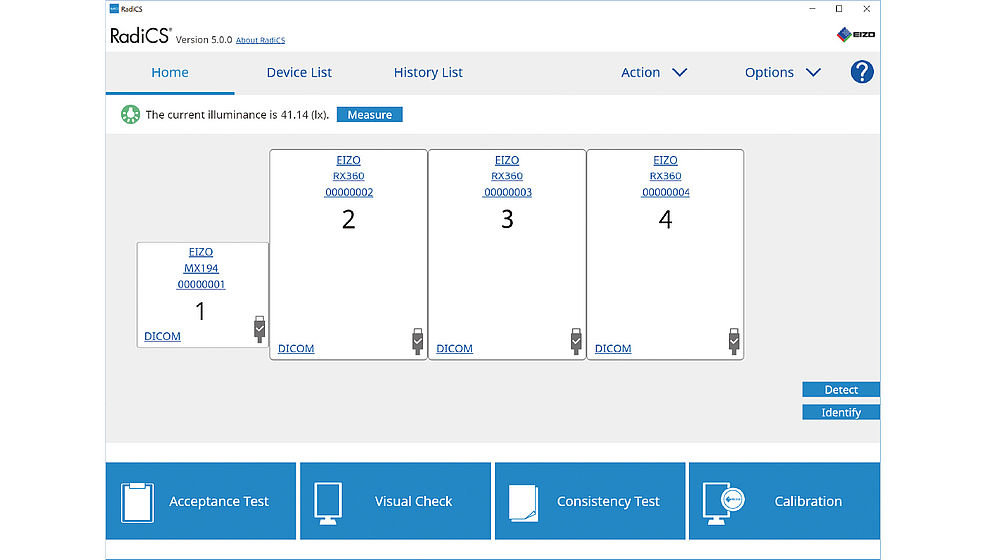

RadiCS pozwala od początku do końca przeprowadzić proces kontroli jakości monitorów, od kalibracji, przez walidację, aż po testy zgodności i niezmienności parametrów. Oprogramowanie jest proste i przyjazne w obsłudze, a w dodatku potrafi w pełni automatycznie wykonywać pomiary testowe. RadiCS pozwala również kontrolować funkcje Work-and-Flow – m.in. funkcję Point-and-Focus, dzięki której radiolog może szybko zaznaczyć wybrany fragment obrazu za pomocą myszy lub klawiatury, aby go przybliżyć.

Oprogramowanie do kalibracji i zarządzania monitorami RadiForce